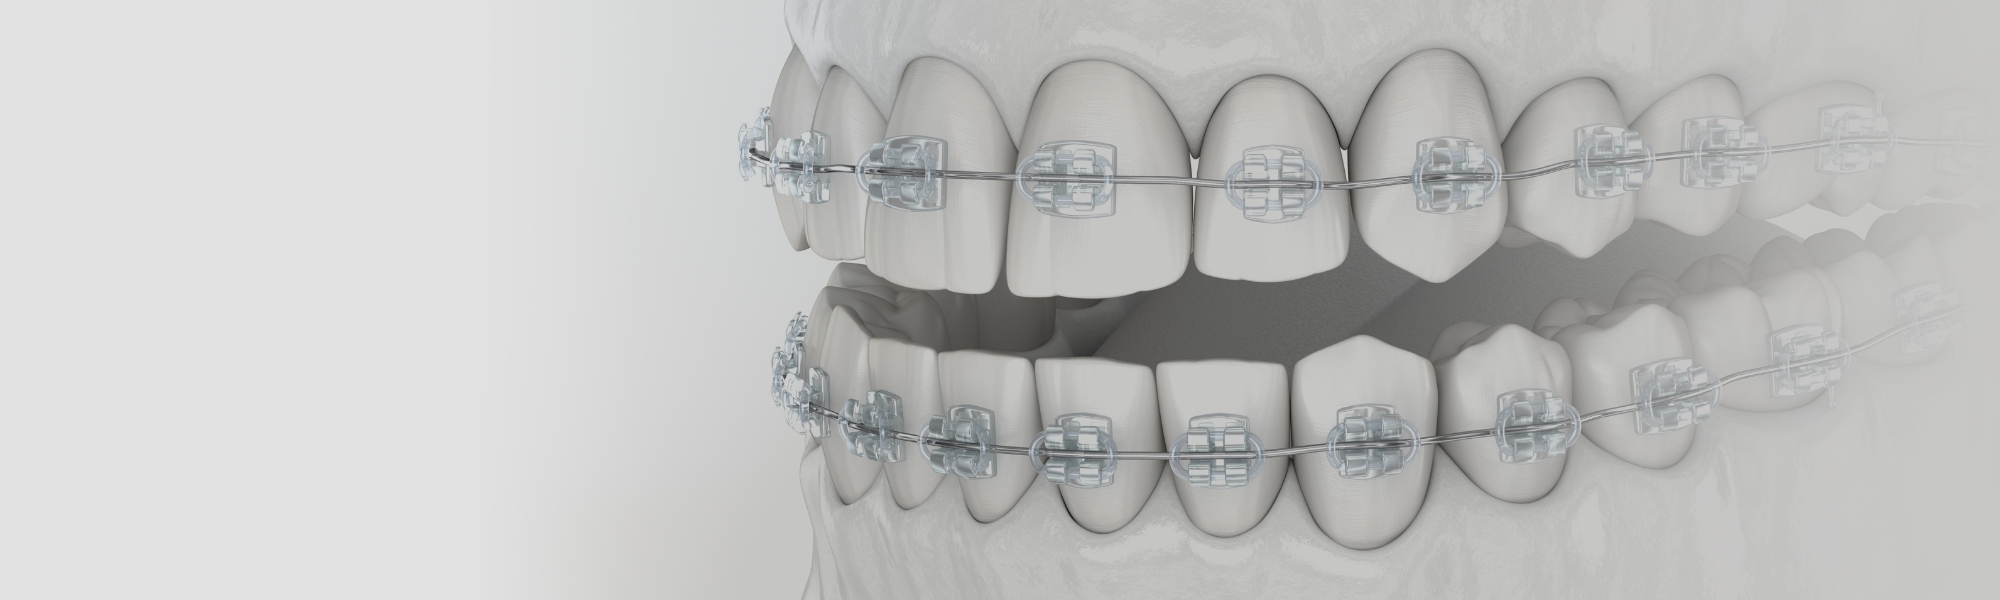

- 動的治療

- 矯正装置による歯の移動を行います。